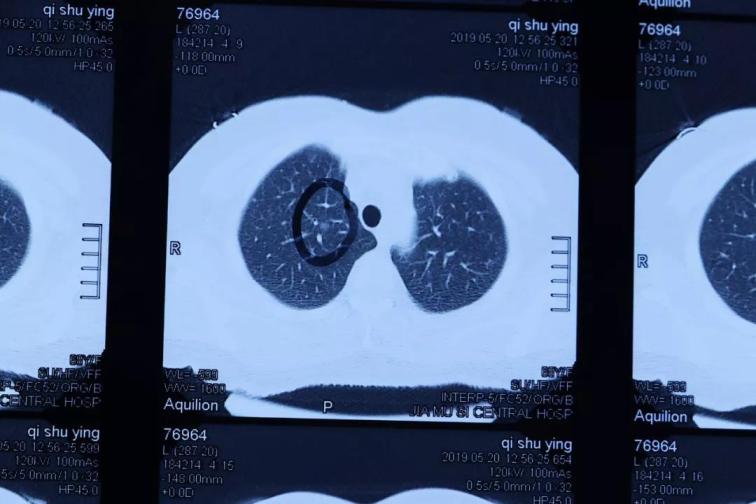

佳木斯大學(xué)宏大醫(yī)院胸心血管外科,在2019年6月收治了一名右肺上葉微小結(jié)節(jié),直徑約4mmX3mm和3X2mm等大小的肺磨玻璃癥。病人女性,63歲,沒(méi)有明顯癥狀,在體檢中發(fā)現(xiàn)小結(jié)節(jié)后,前后去過(guò)北京協(xié)和醫(yī)院和哈醫(yī)大附屬醫(yī)院就診,沒(méi)有明確診斷,進(jìn)行定期復(fù)查處理。來(lái)我院就診在心胸外科,經(jīng)過(guò)入院后常規(guī)檢查,胸CT掃描薄層小結(jié)節(jié)分析,疑診右肺上葉多發(fā)微小結(jié)節(jié),有癌變傾向。經(jīng)過(guò)術(shù)前準(zhǔn)備,周鋼主任手術(shù)團(tuán)隊(duì),在全麻下行胸腔鏡微創(chuàng)右肺上葉切除術(shù),手術(shù)順利。

目前國(guó)內(nèi)外肺小結(jié)節(jié)外科手術(shù)的最小標(biāo)準(zhǔn)在8mm以上,且多為實(shí)性結(jié)節(jié),對(duì)肺小結(jié)節(jié)的手術(shù)定位和病理檢查、臨床診斷是公認(rèn)的技術(shù)難題。佳木斯大學(xué)宏大醫(yī)院胸心血管外科和病理科,通過(guò)影像學(xué)檢查對(duì)肺小于5mm微小小結(jié)節(jié)精準(zhǔn)分析,采用連續(xù)超薄病理切片檢查,診斷了肺小結(jié)節(jié)肺磨玻璃癥,病灶直徑僅僅在4mm和3mm以下,達(dá)到了國(guó)際先進(jìn)水平,填補(bǔ)了黑龍江省微小超早原位肺癌外科微創(chuàng)治療及病理診斷的空白,為肺癌患者早期診斷、早期治療帶來(lái)了福音。CT影像、胸外微創(chuàng)手術(shù)和病理診斷技術(shù)值得推廣,標(biāo)志著佳木斯大學(xué)宏大醫(yī)院胸心血管外科、病理科、影像科具有完成高水準(zhǔn)、高難度的診斷及治療水平。